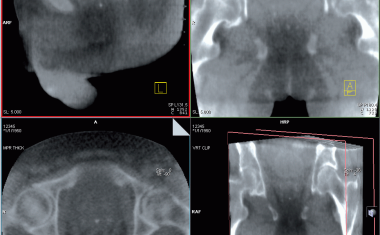

Plötzlicher Herztod: 3D-Bildgebung zeigt mögliche Ursache

Ein Bildgebungsverfahren von Freiburger Forschern liefert Erkenntnisse zu Herzrhythmusstörungen, die den plötzlichen Herztod auslösen können.